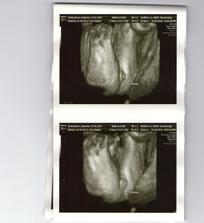

3D - nas poklad

Nas drobcek na 3D

bolo to teraz v nedelu 24.10 a bola som 22 tyzden 5 den.Ale mala je o tyzden popredu tak podla merania lekara bola 23 tyzden 5 den